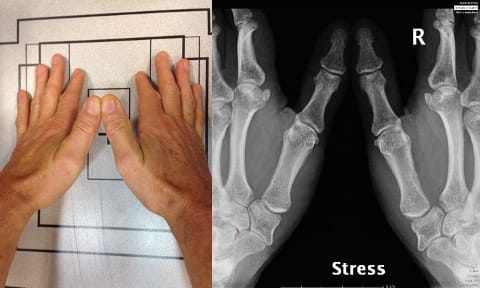

Eaton’s views are the same as Kapandji’s frontal view, except that in the Eaton series the images are comparative (Figure 4), which means that a stress view (Figure 5) is taken so that the joint space can be assessed for any collapse when put under stress.

The value of dynamic views is illustrated very clearly in Fig. 12, showing a Dell stage II, Eaton stage 3, TMA 1, TMI 1, STT 0 joint, which, when seen under stress, suddenly becomes Dell stage II (unchanged) Eaton stage 3 and TMA 3, TMI 1, STT 0 (Figure 13). This demonstrates that Allieu’s classification has greater precision for the TMA [8] Vigouroux F, Rabarin F, Jeudy J, Bigorre N, Saint Cast Y, Pechmajou L, Raimbeau G. Peritrapezial osteoarthritis: Inter – and intraobserver reliability of the Allieu classification. Hand Surg Rehab 36 (2017) 363-367 .